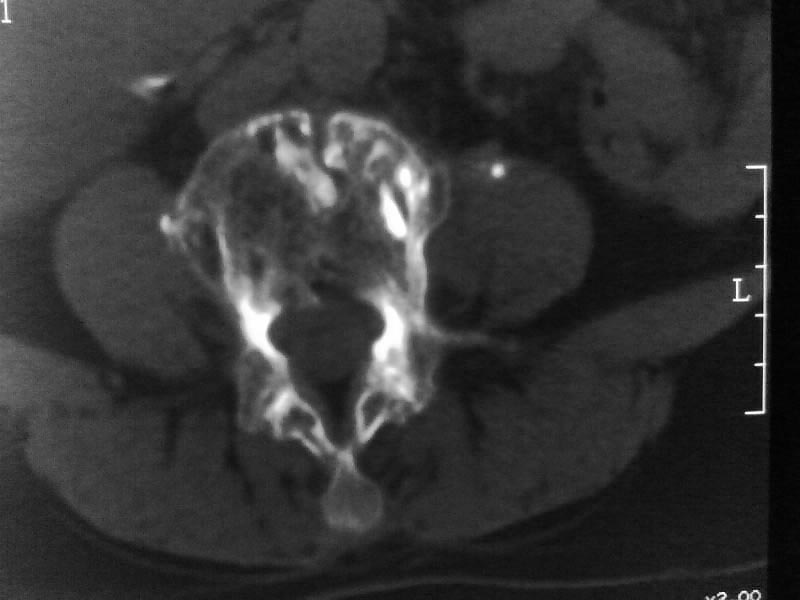

定位相示l2呈楔形改变(ct示陈旧性骨折改变,图像未传),l4.5椎体融合,以下是l4.5ct平扫.请各位看看,

考虑结核(有破坏、硬化及死骨)。

1、三四椎体结核,2、水平骶椎。

1、l1压缩性骨折(陈旧性)。

2、l3、4椎体结核。

就是腰1压缩性骨折,腰3\\4椎体结核(融合),水平骶椎.

支持 l1椎体陈旧性压缩性骨折;l3、4椎体结核(融合);水平骶椎。